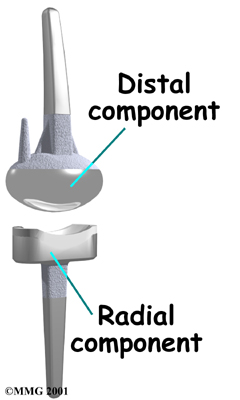

Modern artificial wrist joints are made of metal and plastic. The part that fits against the end of the radius bone of the forearm is called the radial component. It is made up of two pieces. A flat metal piece is placed on the front part of the radius. It has a stem that attaches down into the canal of the bone. A plastic cup fits onto the metal piece, forming a socket for the artificial wrist joint.

The part that replaces the small wrist bones is called the distal component. This piece is made completely of metal. It is globe shaped to fit into the plastic socket on the end of the radius. The metal distal component is attached by two metal stems that fit into the hollow bone marrow cavities of the carpal and metacarpal bones of the hand.

The plastic used in artificial joints is tough and slick. It allows the two pieces of the new joint to glide easily against each other as you move your wrist. The ball and socket allow movement of the wrist in all directions.